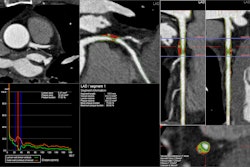

Olympus will initially launch the software for three applications: thoracic surgery, liver surgery, and urologic surgery. In thoracic surgery, the software can convert 2D CT/MRI images into 3D models, which will help in planning of lung cancer and thoracic procedures, as well as reducing invasive approaches, the vendors said.

The platform can also help general and hepatobiliary surgeons visualize liver anatomy, practice ahead and plan for liver-sparing surgeries. For urologic surgery applications, the software can assist in minimally invasive nephrectomies by accurately assessing the size, location, and shape of tumors, cysts, or other abnormalities, according to the firms.